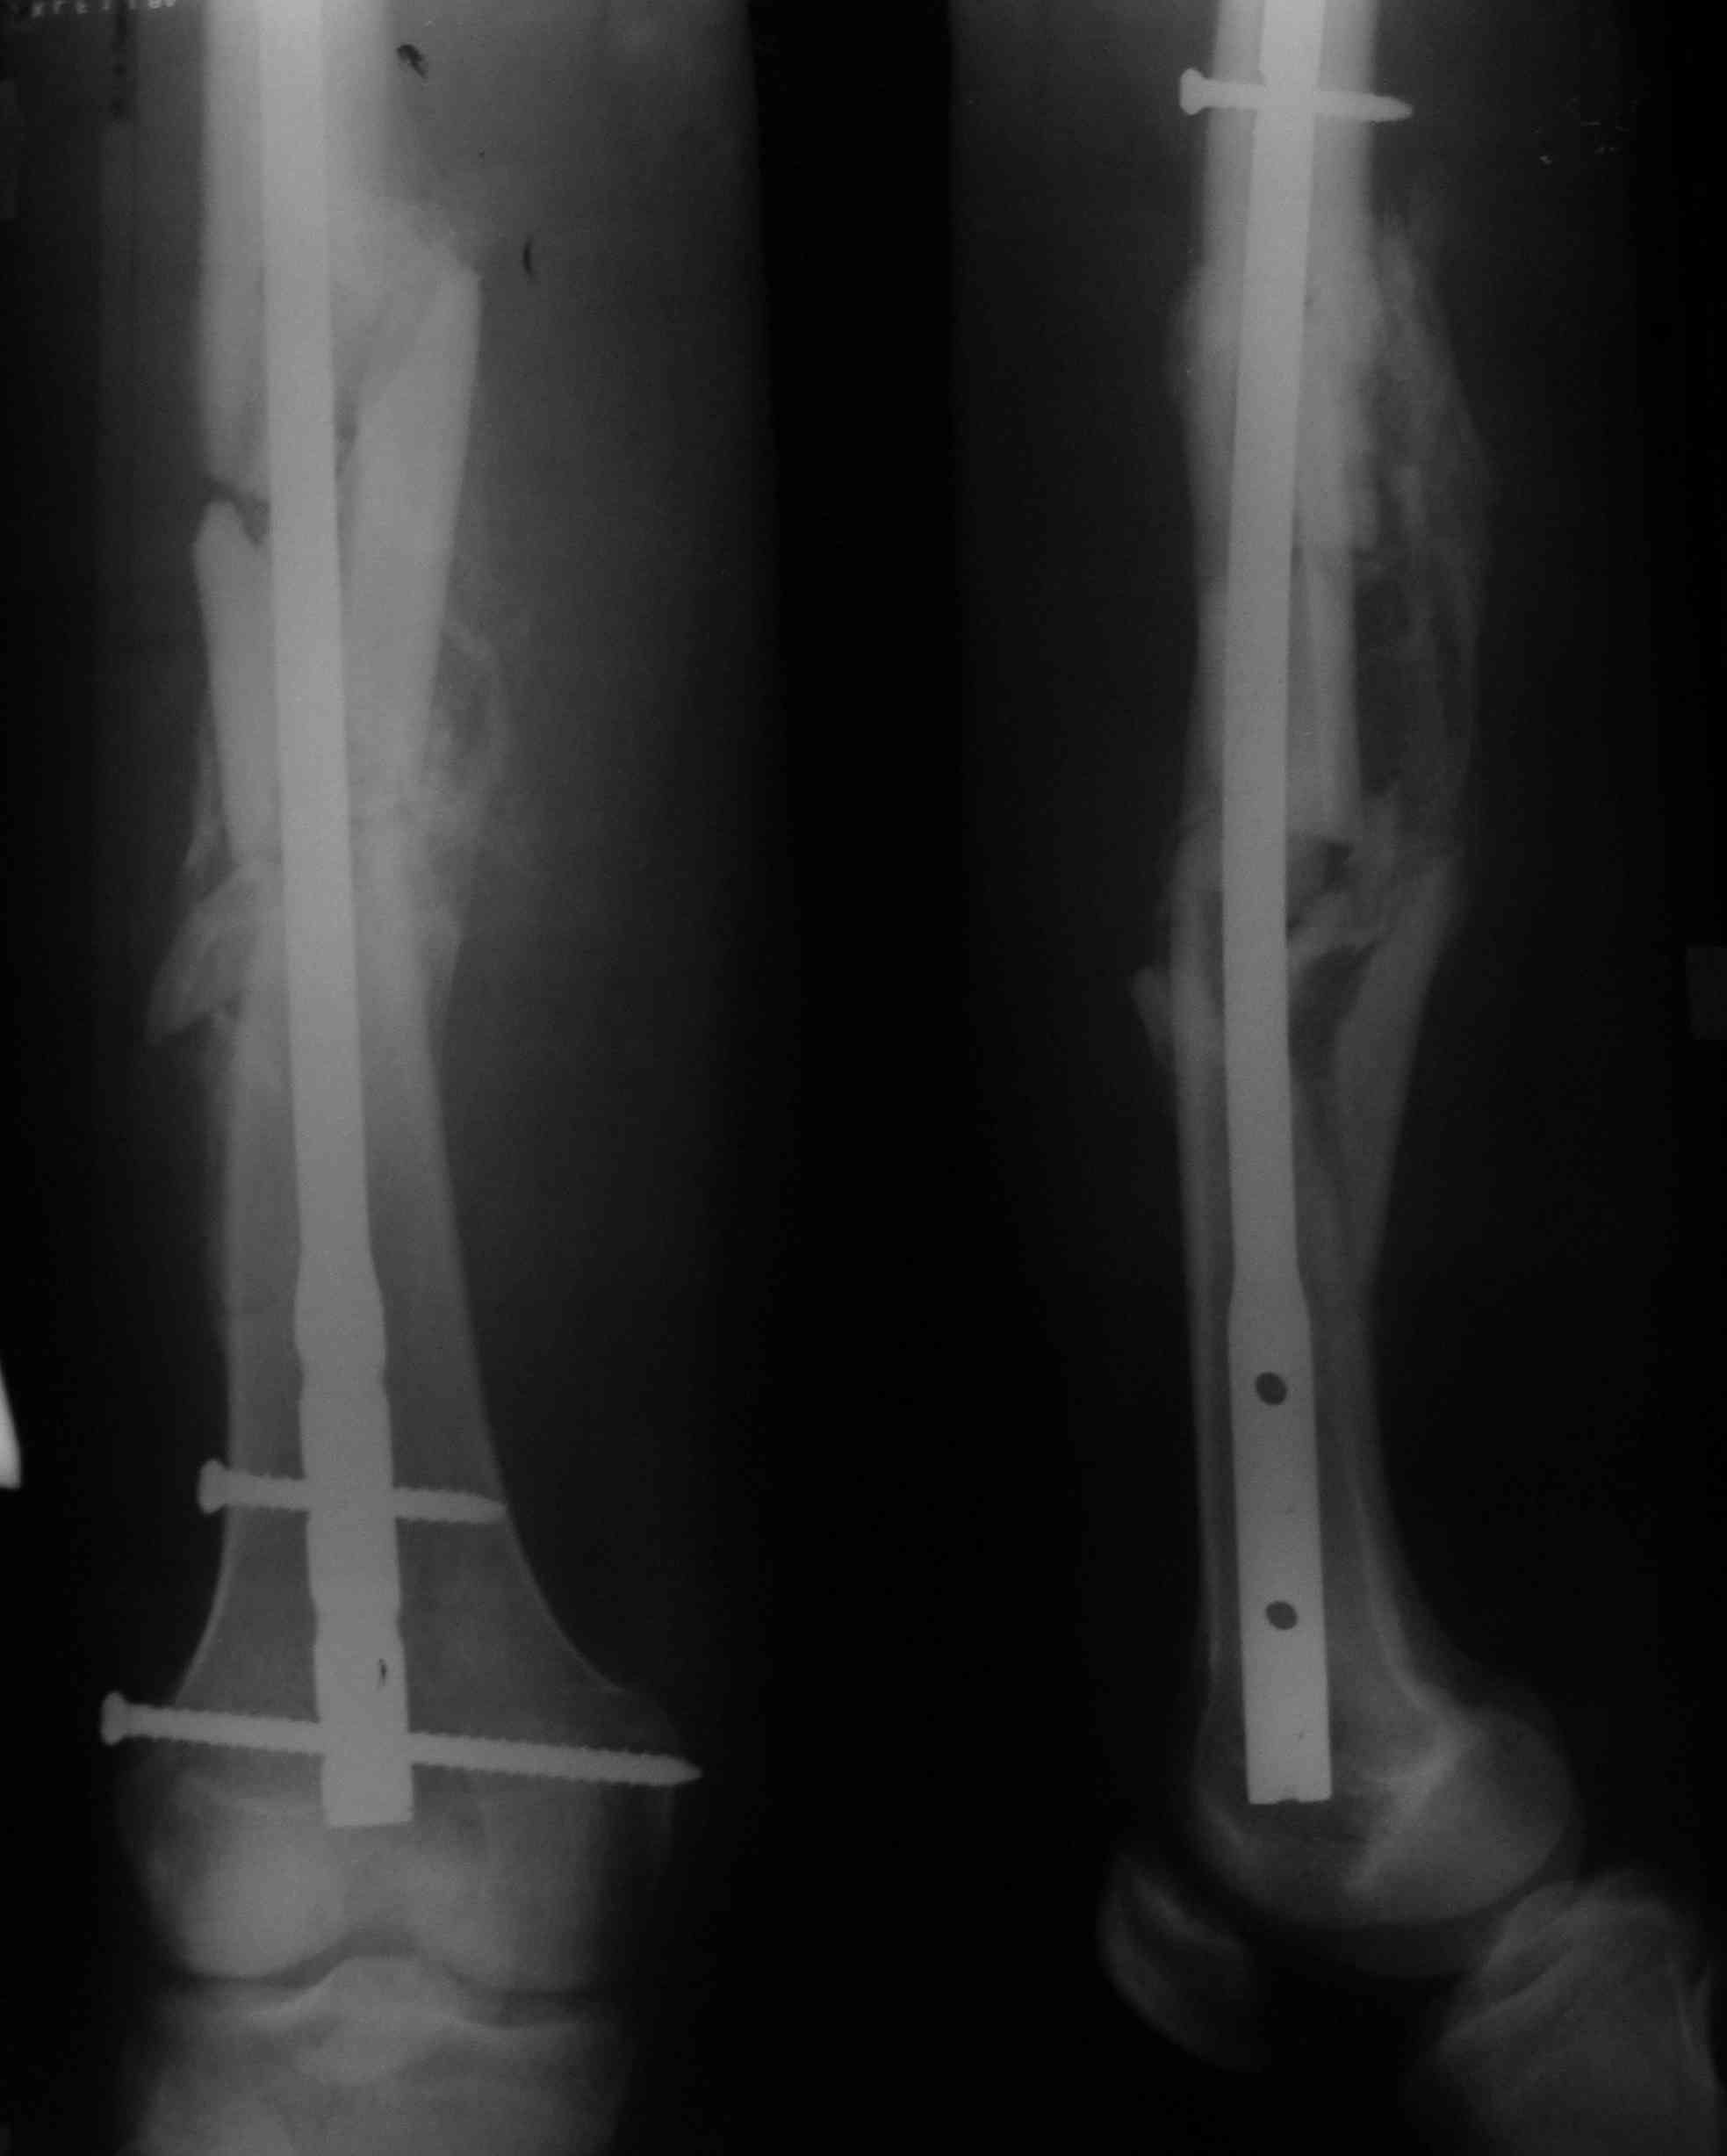

Вот я и сходил к травматологу в поликлинику. Радует, что хоть снимки теперь на руках, можно выложить, что собственно я и сделал. Снимал фотиком, так что если что не разобрать - постараюсь лучше сделать. Скажите, какие дальнейшие действия по нагрузке ноги? А то информации практически нет. Врач принимал другой, не тот что карту мою составлял. Этот только сделал снимок и записал на дальнейший прием в первому врачу. Врач, который проводил операцию, сейчас в отпуске. В больнице травматологи сказали, что можно давать нагрузку, разрабатывать ногу, но потихоньку, и очень аккуратно, а то колено после 2-х месяцев слабое. Оно в действительности, так и есть. Но на двух ногах я уже после 7 недели стоял. только ходил на одной ноге с костылями. Щас пытаюсь ходить с одним костылем, который просто в руке держится. Колено хоть и держит при опоре на костыль, но не долго. Где-то 1-2 секунды. Потом начинает слабеть и болеть. В принципе, чтобы сделать шаг, хватает. Но вот подняться на ступеньку (они пока еще есть в совдеповских квартирах) это сложно. Поэтому в другой руке ношу обычный деревянный костыль.

Отсюда вопрос... Какая нагрузка на ногу возможна при таком состоянии, как на снимках? Колено ведь у человека способно держать очень большую нагрузку. но ведь есть же какие-то ограничения в связи с переломом? После того, как восстановится колено, можно ли будет ходить без костылей, просто хромая на одну ногу? Или до полного сращения не стоит?

Вы так и не указали дату операции. Предполагаю, что прошло больше 2 мес.

На снимках все хорошо.

Нагрузка возможна та, которая получается без хромоты. Т.е. если можете идти, не хромая, без костылей и трости - на здоровье. Если сильно хромаете - пользуйтесь дополнительной опорой в противоположной руке. Движения в колене надо уже разработать, уже должны свободно садиться на корточки.

Да, вы правы, снимок сделан на 10-й неделе (после 2 мес.). Вот только выкладывал еще при выписке снимки, с комментариями на изображении. Видать, было отредактировано. Ну хоть эти остались... и ладно...

Ходить с тростью с каждым днем получается все лучше. И в плане равновессия моего, и в плане колена. Но дальше квартиры пока боюсь. Уже колено болит меньше, но полную нагрузку пока не выдержит. А вот на корточки сесть не получиться. К 8 неделе уже нога дальше чем на 90 градусов не сгибалась. Если пытаться и дальше согнуть - появляются боли в самом конце бедра в районе колена. Там еще через кожу можно нащупать заостренный конец болта. Сначала думал на этот болт, но в больнице сказали, что раньше чем через год об этом разговора быть не может. Так что пока разрабатываю колено, может и лучше будет... Выложил опять снимок, там болты лучше видно. Скажите, это нормально болт установлен?